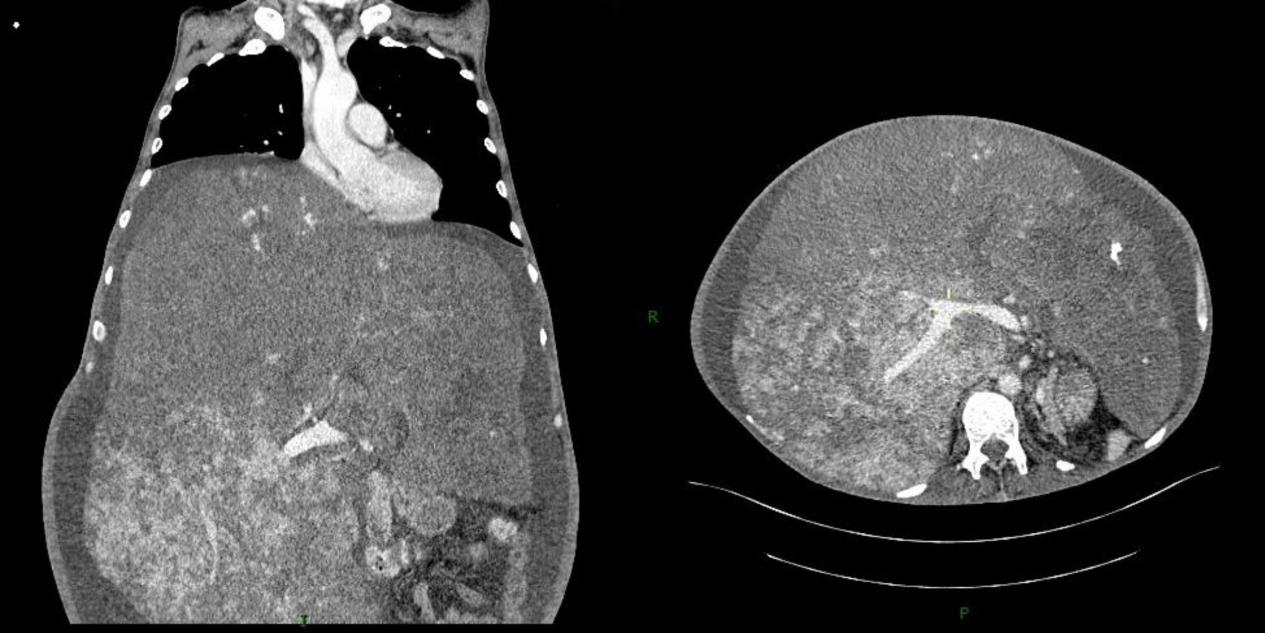

| 图 3 腹部增强CT检查 |